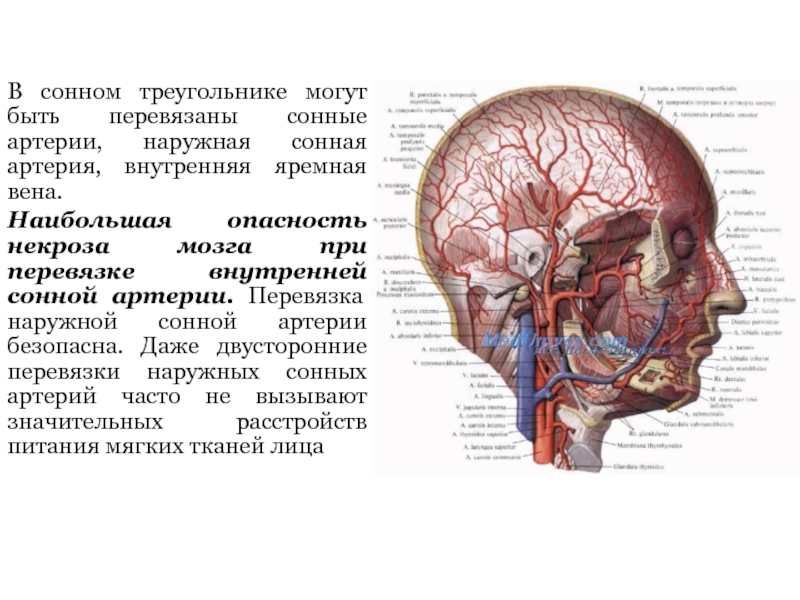

Анатомия внутренней яремной вены: КТ изображения